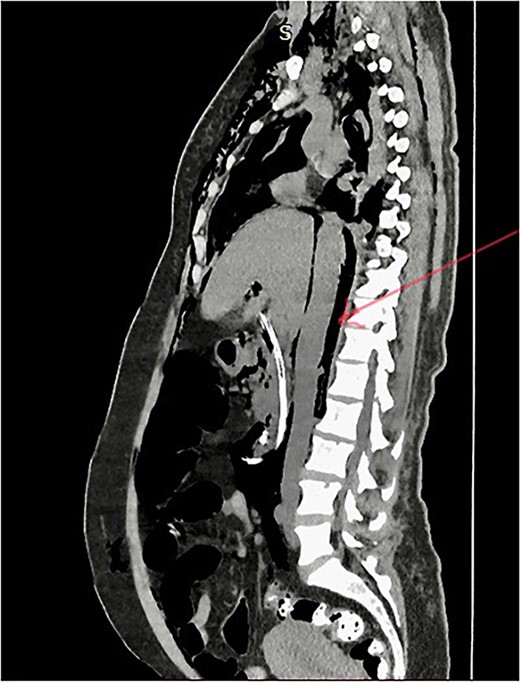

She has undergone a semi-elective ERCP in a semi-prone position, under sedation with propofol target-controlled infusion. Major papillae identified with side viewing endoscopy. Guidewire was inserted into CBD, and a cholangiogram was done. It showed dilated CBD up to 1.3 cm, mild dilated hepatic ducts, and a large radiolucent area in the distal CBD (around 1.5 cm). Sphincterotomy was done with a sphincterotome, and the ampulla was dilated up to 1.5 cm with a balloon dilator. Then, a balloon retrieval was attempted and failed, probably due to a stone sticking to the CBD wall. Then, a mechanical lithotripter was used to break the stone, but it failed, damaging the instrument. During the procedure, her oxygen saturation dropped to 75–80%, and she developed surgical emphysema in the face, neck, and upper chest region. In addition, she developed abdominal distention as well. Immediately, she underwent CBD stenting with a 12-cm, 10 French Gauge double pigtail biliary stent and changed her position to supine. Then, she was intubated with rapid sequence induction, and a nasogastric tube was inserted and transferred to the surgical intensive care unit. Post-ERCP, non-contrast computed tomography (NCCT) of the abdomen and chest showed extensive pneumo-peritoneum and retroperitoneal gas with subcutaneous emphysema (Figs 2 and 3). There was no evidence of air leakage on NCCT and no clinical features of peritonitis on subsequent days. So she was managed non-surgically with nasogastric tube (NG), nil by mouth, intravenous fluids with intravenous antibiotics. Clear fluid was started after 24 hours slowly via NG.

Post-ERCP NCCT abdomen shows pneumo-retroperitoneum (red arrow).